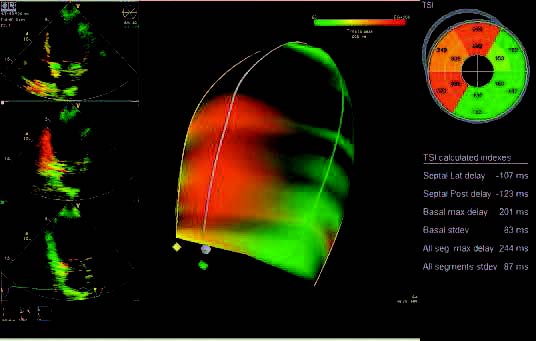

GE Vivid 7 Imaging Modes

- Tissue Velocity Imaging

- Tissue Tracking